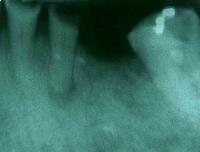

Una paciente femenina de 75 años de edad, se presentó al servicio de patología de la Universidad Santa María (Caracas, Venezuela). Al análisis intraoral, se observó la pérdida total de la corona clínica del canino inferior izquierdo. En el análisis radiográfico (Radiografía panorámica y periapical) se observó una imagen radiolúcida, ovoide, única, a nivel del eje axial de dicho canino, con cortical bien definida. La lesión era de aproximadamente 1,2 cm. de diámetro, y fue asociada a un quiste periapical. Se realizó la exodoncia del resto radicular del canino, y se tomó una muestra de la lesión para realizar un posterior estudio histopatológico. Se envió al histopatólogo una muestra conjunta de epitelio, tejido conjuntivo y zonas de abceso.

Figura 2: Estudio radiográfico en donde se puede observar la lesión periapical